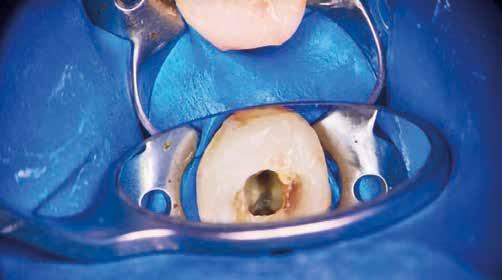

Krell és Caplan kutatásában 2086 repedt fogat vizsgáltak meg. A vizsgált fogak között leggyakrabban a második alsó nagyőrlőfogak (36%), majd ezt követően az első alsó nagyőrlők (27%), és végül az első felső nagyőrlők (18%) fordultak elő. A kutatási eredményeik szerint a fogbél állapota nem befolyásolta jelentős mértékben a kezelés várható kimenetelét. (Irreverzibilis pulpitis 85%; necrosis 80%; korábban gyökérkezelt 74%). A kimenetel szempontjából ugyanígy indifferens volt a páciensek neme, életkora, a kezelés időpontja, a fog pozíciója, a fog helyreállítása során használt anyag típusa, valamint az érintett fogfelszínek száma. 2014 júliusában egy 45 éves hölgy páciens azzal a panasszal kereste fel a rendelőnket, hogy nagyjából 10 napja egy fájdalmas duzzanat alakult ki a jobb felső első kisőrlője koronája mellett (14). A klinikai vizsgálat során egy amalgámtömést találtunk a panaszos fogban. A tömés széli zárása nem volt megfelelő, a disztális záróléc és a tömés között rést tapasztaltunk. A fog disztobukkális és linguális felszíne mellett 8 mm-es csontos tasakokat mértünk. A periapikális felvételen az 14-es foggyökér disztális felszínének megfelelően vertikális irányú radiolucens felritkulást észleltünk. A klinikai vizsgálat során a mesiális zárólécet kettéválasztó törésvonalat detektáltunk (17–18. ábra). A fogszenzibilitás vizsgálata során negatív eredményt kaptunk. A páciensnek ismertettük az elérhető terápiás lehetőségeket: 1, a 14-es fog eltávolítása, majd a foghiány 3 tagú cementezett híddal történő pótlása; 2, a 14-es fog eltávolítása, kemény- és lágyszöveti augmentáció, majd implantátum behelyezése; 3, a 14-es fog gyökérkezelése, gyökértömése és ezt követően a csücsökborítást biztosító restaurátum készítése. Arra is felhívtuk a páciens figyelmét, hogy a 3. terápiás lehetőség választása esetén nem tudjuk a fogmegtartás sikerességét garantálni, de végül – főként anyagi okok miatt – mégis ezt a terápiás opciót választotta. Fontos megjegyezni, hogy a repedt fogak ellátási lehetőségeit a törésvonal mélysége, elhelyezkedése, lefutása nagyban befolyásolja. A kezelés megtervezése során a fog és a fogat körülvevő szövetek állapotával kapcsolatos számtalan különböző faktort kell egyidejűleg figyelembe vennünk. A gyökérkezelést követően a gyökértömést meleg vertikális kondenzációs technikai alkalmazásával készítettük el (19. ábra). A hozzáférési nyílást folyékony és hibrid kompozit tömőanyag segítségével zártuk. A zárás elkészítése során a dr. David Clark által kifejlesztett Bioclear matricarendszert alkalmaztuk. A 6 éves kontroll során készített (2020) röntgenfelvételen a csontos defektus telődése volt megfigyelhető. Ez is a parodontális defektus gyógyulását igazolta (20–21. ábra).

17. ábra: A 14-es fog gyökerének disztális felszíne mellett vertikális csontpusztulásra utaló jelek észlelhetőek. Klinikailag ezen a területen 8 mm mélységű tasakmélységet mértünk. – 18. ábra: A 14-es fog disztális zárólécének megfelelően törésvonal észlelhető, ugyanakkor a csücskök teljes szeparálódására utaló jelek nem láthatóak. Az amalgámtömés eltávolítását követően jól megfigyelhető volt a törésvonal teljes lefutása. – 19. ábra: A gyökértömés elkészítése során meleg vertikális kondenzációs technikát alkalmaztunk. A felvételeken oldalcsatornák jelenlétére utaló jelek is észlelhetőek. – 20–21. ábra: A 2020-ban készült kontrollfelvételeken jól látható a csontos defektus telődése. A radiológiai jelek alapján (jól lekövethető gyökérhártyarés) a parodontális ligamentumok regenerációját is vélelmezzük.